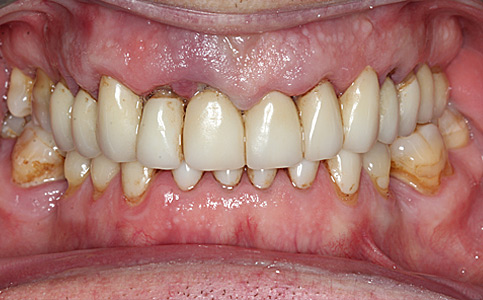

Pacjent zgłosił się do naszego Centrum stomatologii i Ortodoncji FRESHmed w Katowicach w celu poprawnia estetyki swojego uśmiechu. Po konsultacji i dokładnej diagnostyce, usunięto zęby dolne z powodu duzej ruchomości. Zęby zostały zastąpione 6 implantami zębowymi, na których odbudowano cały łuk zębowy dolny metodą All-on-6. Poprawę kształtu i koloru zębów górnych uzyskano poprzez zacementowanie koron pełnoceramicznych.

Zobacz efekty przeciągając suwak w prawo lub w lewo.